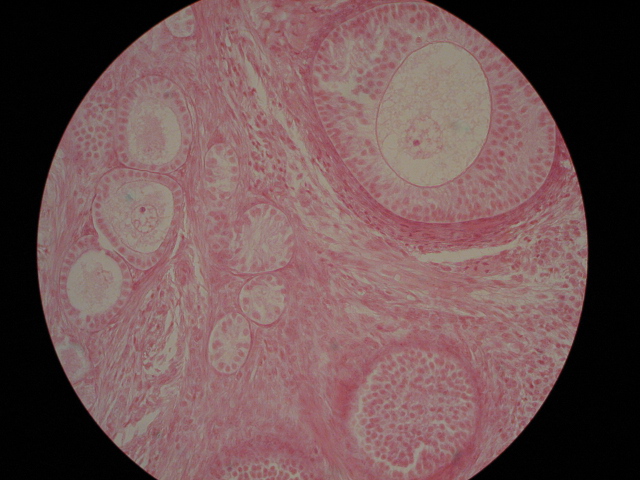

| Primary & Secondary follicles | How many different follicles can you name?,  |